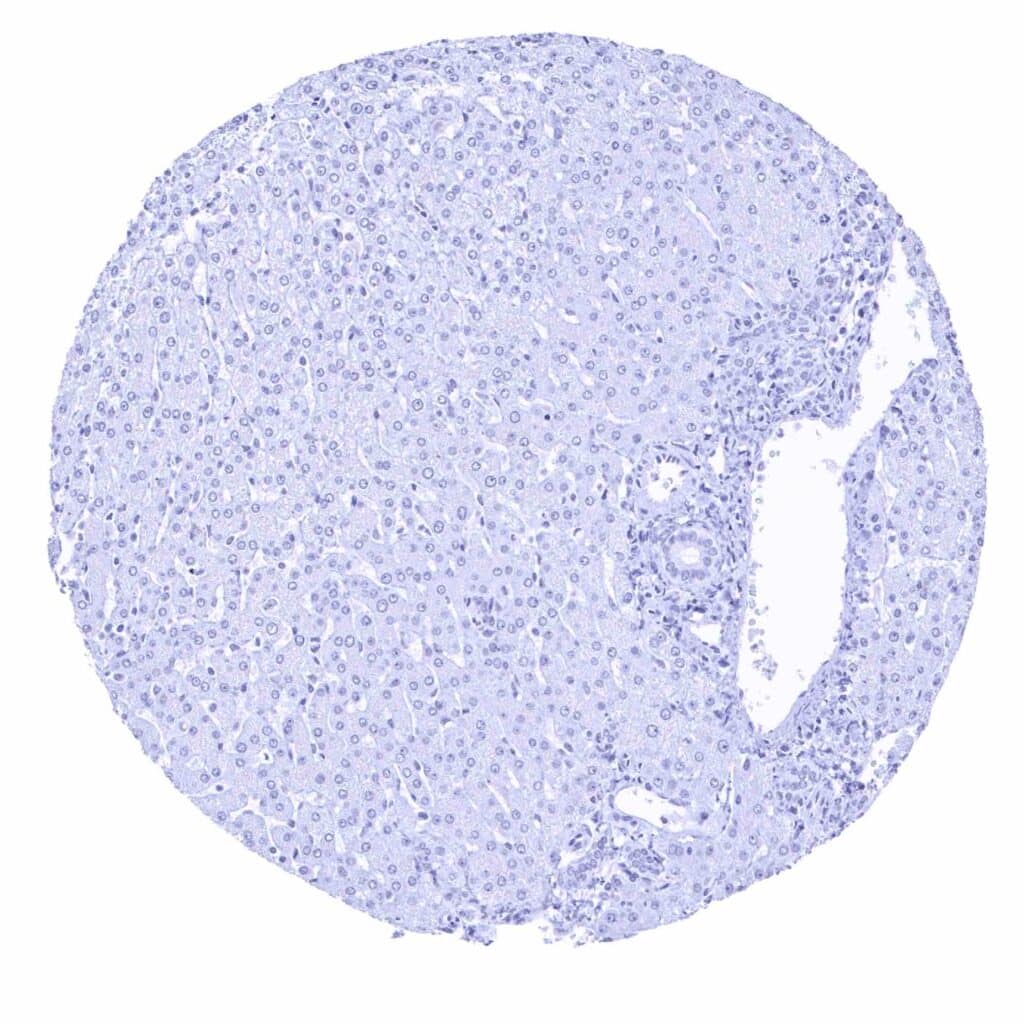

Liver